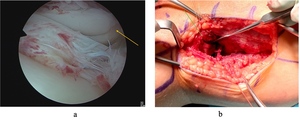

Arthroscopy revealed an irreducible bucket handle tear of the lateral meniscus. Visualization of the Busch-Hoffa fracture was not possible at this stage (Fig 3). A lateral approach to the knee was performed utilizing the interval between biceps femoris and the iliotibial band. Care was taken to protect the common peroneal nerve. The posterolateral capsule was exposed and an arthrotomy was performed. Capsular stay sutures aided retraction and exposure (Fig 3). The fracture fragment was identified and it was noted that a partially torn popliteus tendon was incarcerated in the fracture site (Fig 4). The popliteus tendon was removed from the fracture site and the fracture fragments were reduced anatomically. Two 2mm headless compression screws were used to stabilize the fracture. Subsequently, arthroscopy was resumed, and reduction of the lateral meniscal bucket handle tear was now possible. This was repaired with two all-inside sutures.

_irreducible_lateral_meniscus_tear_with_the_busch-hoffa_fractu.jpeg)